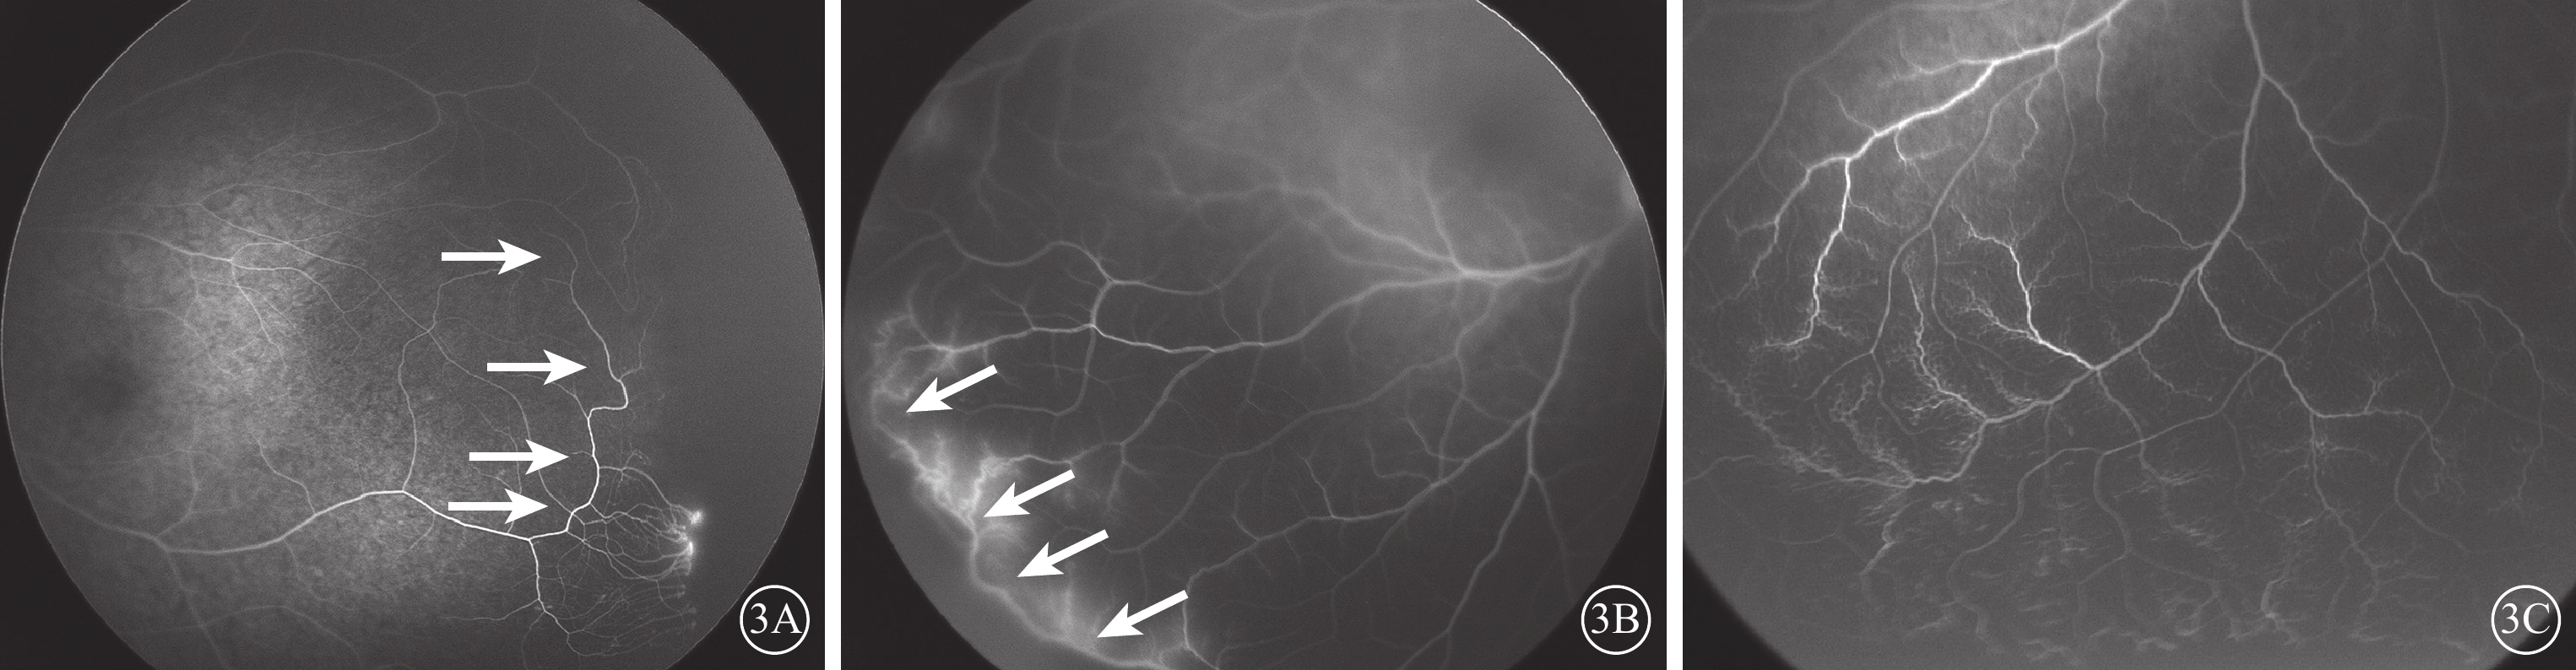

所有患兒ROP均完成自然退行,嵴樣病變逐漸變平消退,視網膜血管向周邊生長進一步血管化。患眼平均臂-視網膜循環時間(A-RCT)為(8.06±2.81)s。動脈前期脈絡膜毛細血管多呈正常小葉狀充盈,脈絡膜大血管旁無毛細血管顯影呈線狀充盈(圖2A)9例(21.95%,9/41)。存在后極部視網膜動脈紆曲(圖2B)32只眼(39.02%,32/82)。在退行開始后完成視網膜血管化區域內(初始嵴與血管化末端間區域),末梢視網膜血管分支增多,由正常錐形2分支變為3分支或4分支(圖2C)45只眼(54.88%,45/82);視網膜末梢血管正常生理性彎曲消失,走行平直(圖2C)27只眼(32.93%,27/82);于初始嵴位置見環狀血管(圖3A)45只眼(54.88%,45/82);視網膜血管化終末位置動靜脈吻合形成分流(圖3B)18只眼(21.95%,18/82);部分外周血管周圍毛細血管床丟失(圖3C)46只眼(56.10%,46/82)。造影晚期血管末梢出現點狀或線狀熒光素滲漏(圖3A,圖4A)23只眼(28.05%,23/82)。黃斑中心凹無血管區縮小、黃斑區弱熒光等黃斑異常(圖4B)28只眼(34.15%,28/82),其中視網膜血管向顳側牽拉、黃斑移位(圖4C)1只眼。退行前嵴呈切跡樣(圖5A)7只眼(8.54%,7/82),其中退行后切跡處血管化欠佳(圖5B)4只眼。